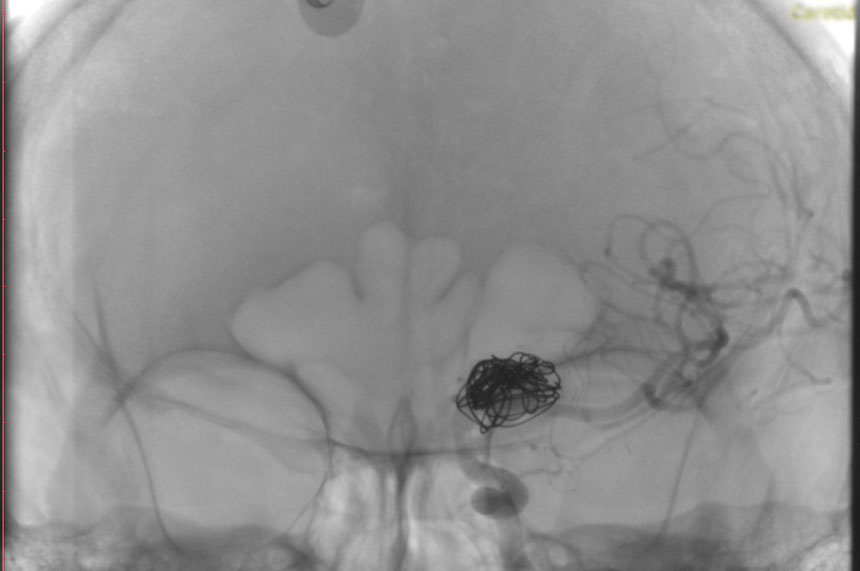

La paciente ingreso al Servicio de Hemodinamia el día martes 11 de febrero con un aneurisma cerebral gigante en la carótida izquierda y se le practicó una embolización; es decir una oclusión por dentro del mismo, donde se colocó un dispositivo denominado coils más un stent diversor de flujo. El procedimiento fue exitoso y contó con la colaboración de médicos neurointervencionistas del Instituto Oulton de la Ciudad de Córdoba.